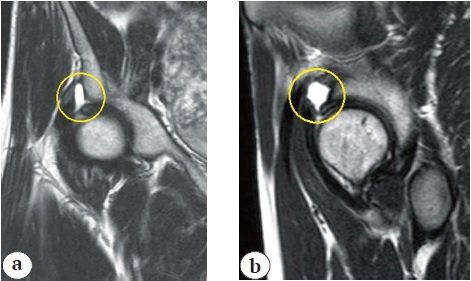

Рис. 2. Предоперационные МРТ: a — коронарный срез Т1; b — сагиттальный срез Т1

Figure 2. Preoperative MRI scans: a — coronary section T1; b — sagittal section T1

Дальнейший анализ срезов МРТ выявил повреждения губы вертлужной впадины, капсулы сустава и передних волокон подвздошно-бедренной связки.